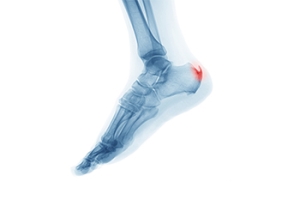

Treatment for Bone Spurs on the Feet

A bone spur, or osteophyte, is an extra growth onto a bone. Spurs can grow on several parts of the feet, including on top of the midfoot, on the back of the heel, or on the toe. Other bone spurs grow under the heel in conjunction with plantar fasciitis. Many people live with bone spurs and feel no pain. Surgical treatment is one way of permanently dealing with painful bone spurs. With a midfoot bump, the spur is removed from both sides of the joint involved. A surgical shoe will be needed for a few weeks after, but you can bear weight right after surgery. For a spur in the back of the heel, the spur will be removed and any damage to the Achilles tendon will be repaired. A cast and crutches will be needed for a few weeks to avoid putting weight on the foot. With a spur on the toe, a small incision will be made before the filing down of the spur with a type of rasp. The site will be bandaged and a surgical shoe may be provided, but weight bearing is OK. For help with painful bone spurs, it is wise to consult with a podiatrist for the right treatment options.

Foot Pain

Foot pain can be extremely painful and debilitating. If you have a foot pain, consult with one of our doctors from Texas. Our doctors will assess your condition and provide you with quality foot and ankle treatment.

Diagnosis

To figure out the cause of foot pain, podiatrists utilize several different methods. This can range from simple visual inspections and sensation tests to X-rays and MRI scans. Prior medical history, family medical history, and any recent physical traumatic events will all be taken into consideration for a proper diagnosis.

Treatment depends upon the cause of the foot pain. Whether it is resting, staying off the foot, or having surgery; podiatrists have a number of treatment options available for foot pain.